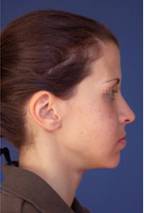

Пациенти с недостатъчност в развитието на долната челюсти брадата (мандибуларна микрогнатия с микрогения) преди и след реконструкции на долната челюст и брадата - случаи на доц. Джоров.